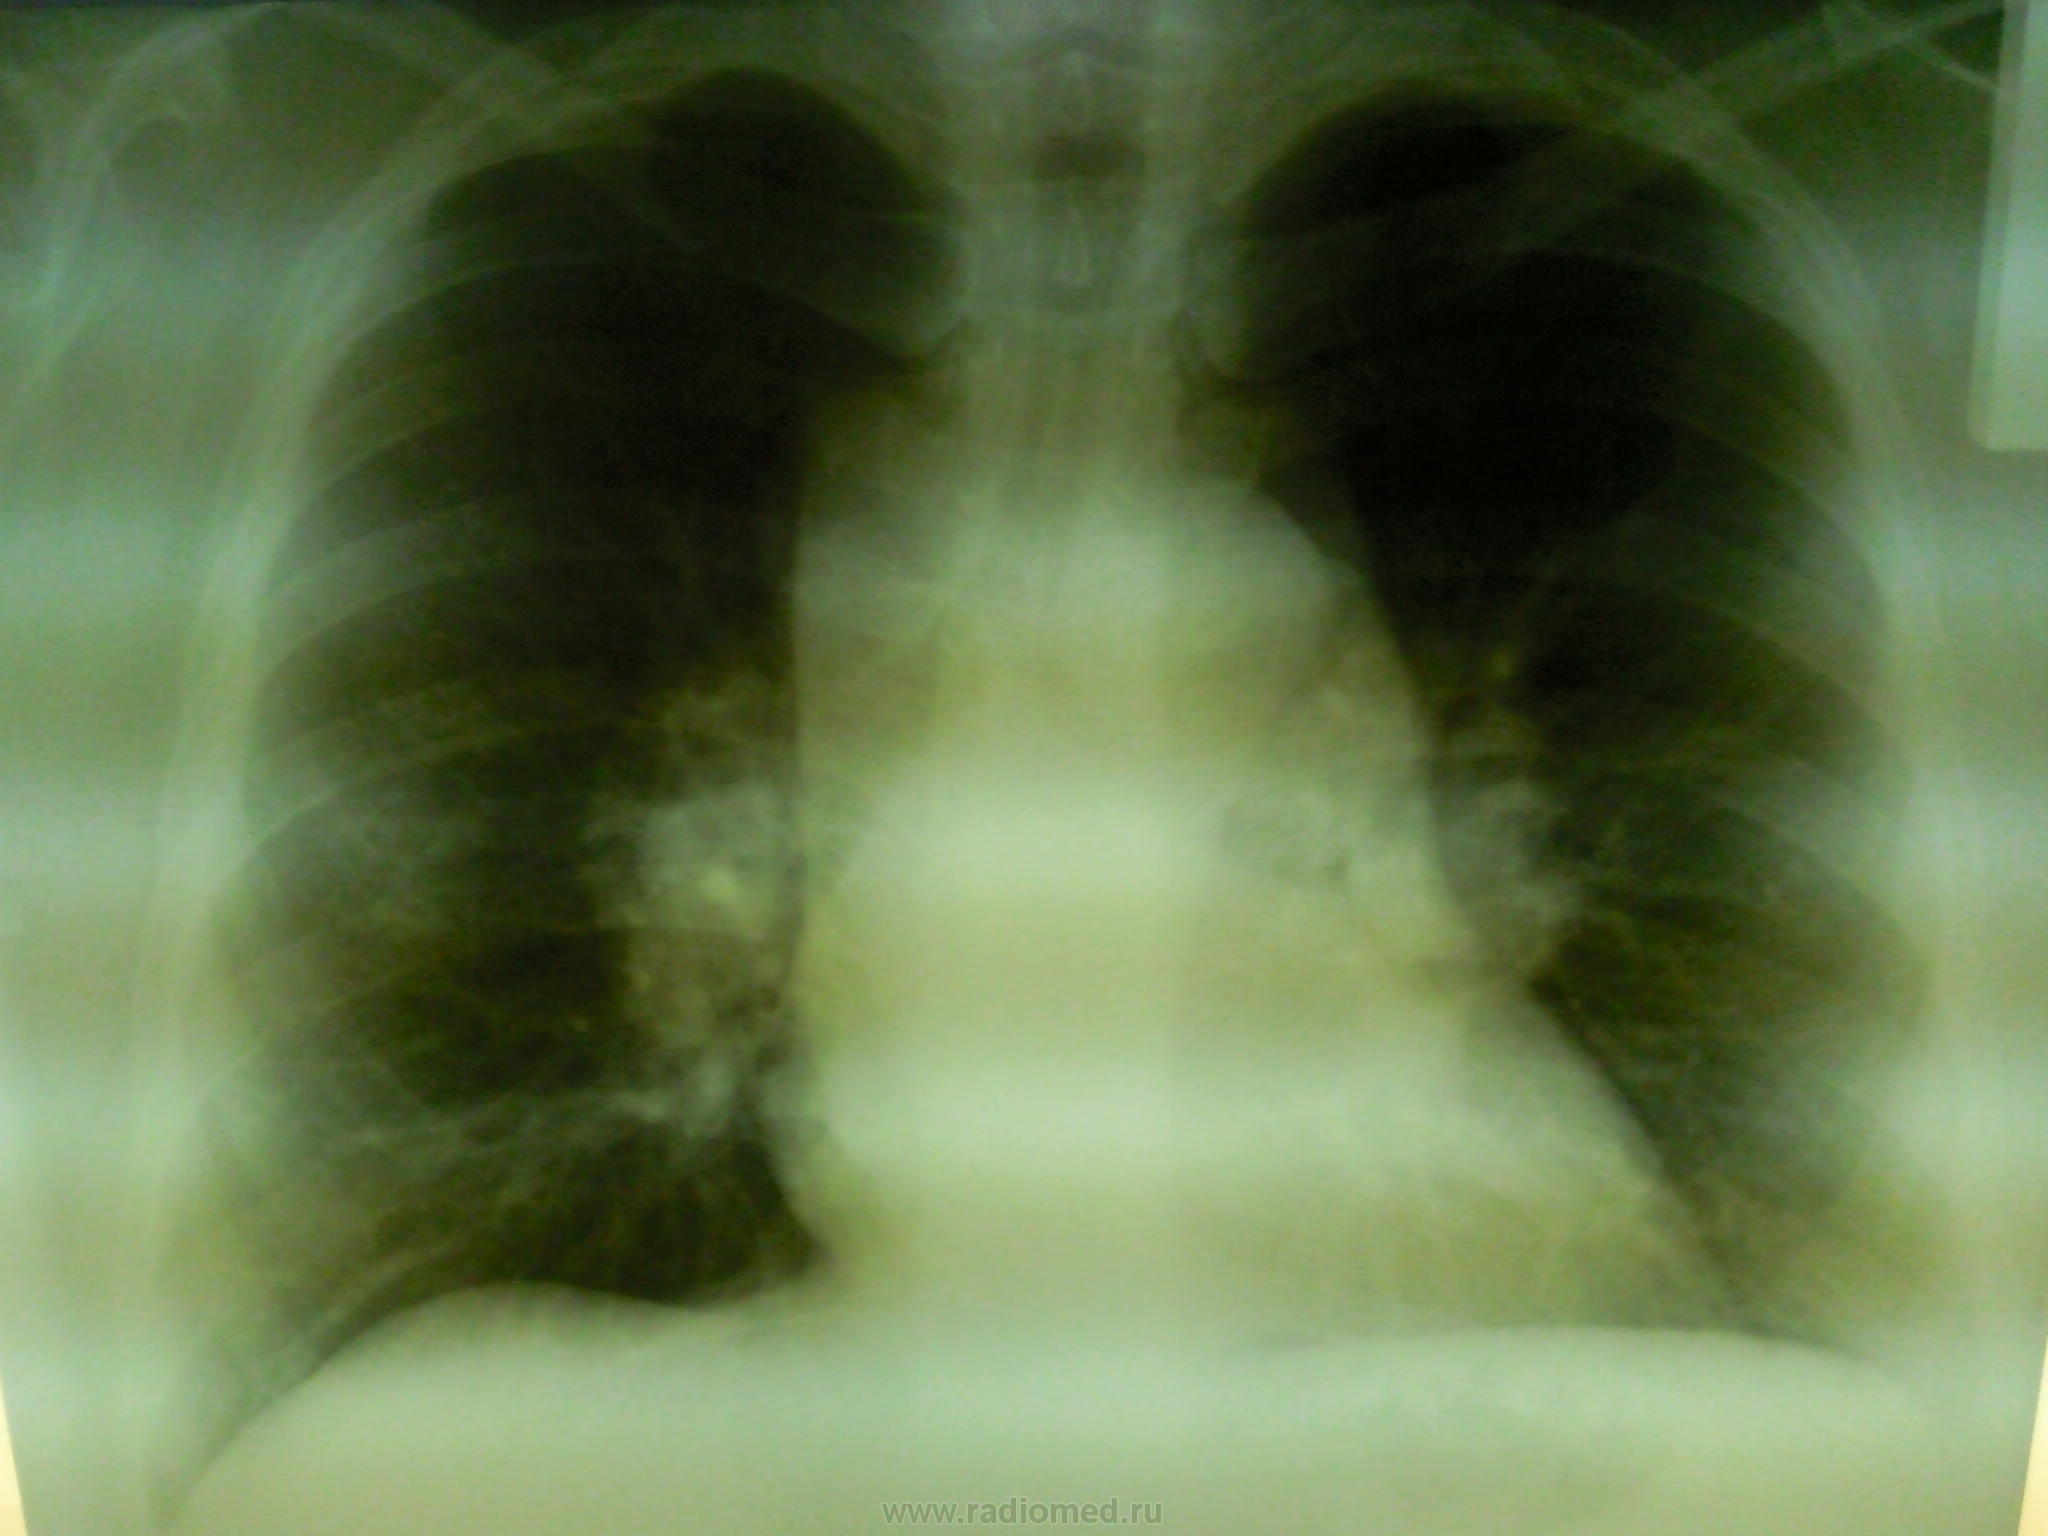

Девушка, 1984 г.р, направлена с флюорографии. Амбулаторная карта, как часто бывает - не нашлась, завели вкладыш. С флюорографии вчерашней, анализов пока нет. По записи уч. терапевта периодически беспокоит покашливание, аускультативно жесткое дыхание, других сдвигов не описано. Обзорный снят на телефон - качество не ахти, боковой не сняли- упущение, сразу оттомографировали, девушку отпустили. Ваши предположения.

А "тенюшка" справа в проекции 6 сегмента мне одной кажется?

Мне тоже показался фокус справа в среднем легочном фоне малоинтенсивный - легочный компонент?

А волнистый контур средостения- лимфоидная ткань?

Боковой не сделали - так уж вышло. Поставил лимфогрануломатоз, ДДС с саркоидозом.

Здесь м. б. и неходжкинская лимфома. Без клинического дообследования не обойтись.

Я бы тоже поставил на первое место лимфогрануломатоз.